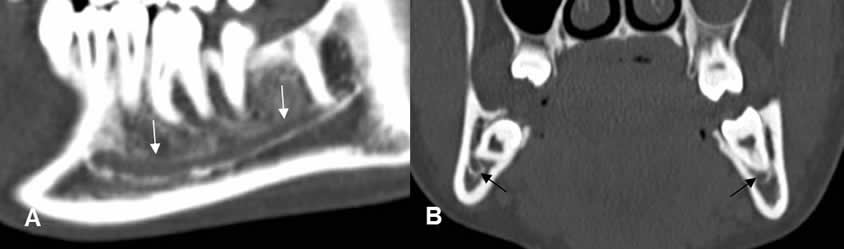

El canal mandibular, ocupa la parte inferior de la mandíbula y se identifica como una estructura ovalada y con bordes escleróticos. (2). (Fig 16).

Fig 16. Canal mandibular normal.

A: TAC reconstrucción sagital y B: TAC reconstrucción coronal. Canal mandibular de bordes densos y que ocupa la parte inferior de la mandíbula.